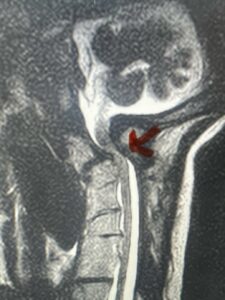

This is a 42 year-old female who presents with severe progressive weakness and numbness and difficulty with balance over a 6-month period. She has a history of having a motor vehicle accident at 5 years old but was never imaged. On exam she was noted to be severely myelopathic. Imaging revealed severe spinal cord compression at the level of C1 (Figs 4a and b).

Fig. 4a: Sagittal T2-weighted cervical MRI demonstrating severe cord compression with myelomalacia of upper cervical spinal cord (red arrow). Notice the increased atlanto-dens interval (red dot).

Fig. 4b: Axial T2-weighted cervical MRI demonstrating severe spinal cord compression from atlanto-axial instability (red arrow)